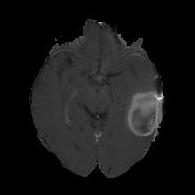

(a) (b) (c) (d)

Boundary Stream:

Fig. 2 demonstrates the output of each of the attention layers in our dedicated boundary stream. In essence, each attention layer progressively localizes the tumor and refines the boundaries. The first attention layer has learned rough estimate of the boundaries around the tumor and localized it, whereas the second and third layers have learned more fine-grained details of the edges and boundaries, refining the localization. Moreover, since our architecture leverages a dilated spatial pyramid pooling to merge the learned feature maps of the regular segmentation stream and the boundary stream, multiscale regional and boundary information have been preserved and fused properly, which has enabled our network to capture the small structural details of the tumor.

(a) (b) (c) (d) (e)

Comparison to Competing Methods:

We have compared the performance of our model against the most popular deep learning-based semantic segmentation networks, U-Net [9] and V-Net [7] (Fig. 3). Our model outperforms both by a considerable margin in all evaluation metrics. In particular, U-Net performs poorly in most cases due to the high false positive of its segmentation predictions, as well as the imprecision of its boundaries. The powerful residual block in the V-Net architecture seems to alleviate these issues to some extent, but V-Net also fails to produce high-quality boundary predictions. The emphasis of learning useful edge-related information during the training of our network appears to effectively regularize the network such that boundary accuracy is improved.